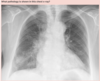

102

**Answer: Chronic Obstructive Pulmonary Disease** ## Footnote In normal subjects, the diaphragm is intersected by the 5th to 7th anterior ribs in the mid-clavicular line - in this patient you can count up to 9 ribs before reaching the diaphragm → hyperexpanded lungs. Flattening of the diaphragm is also observed in this x-ray which is a reliable feature of lung hyperexpansion.